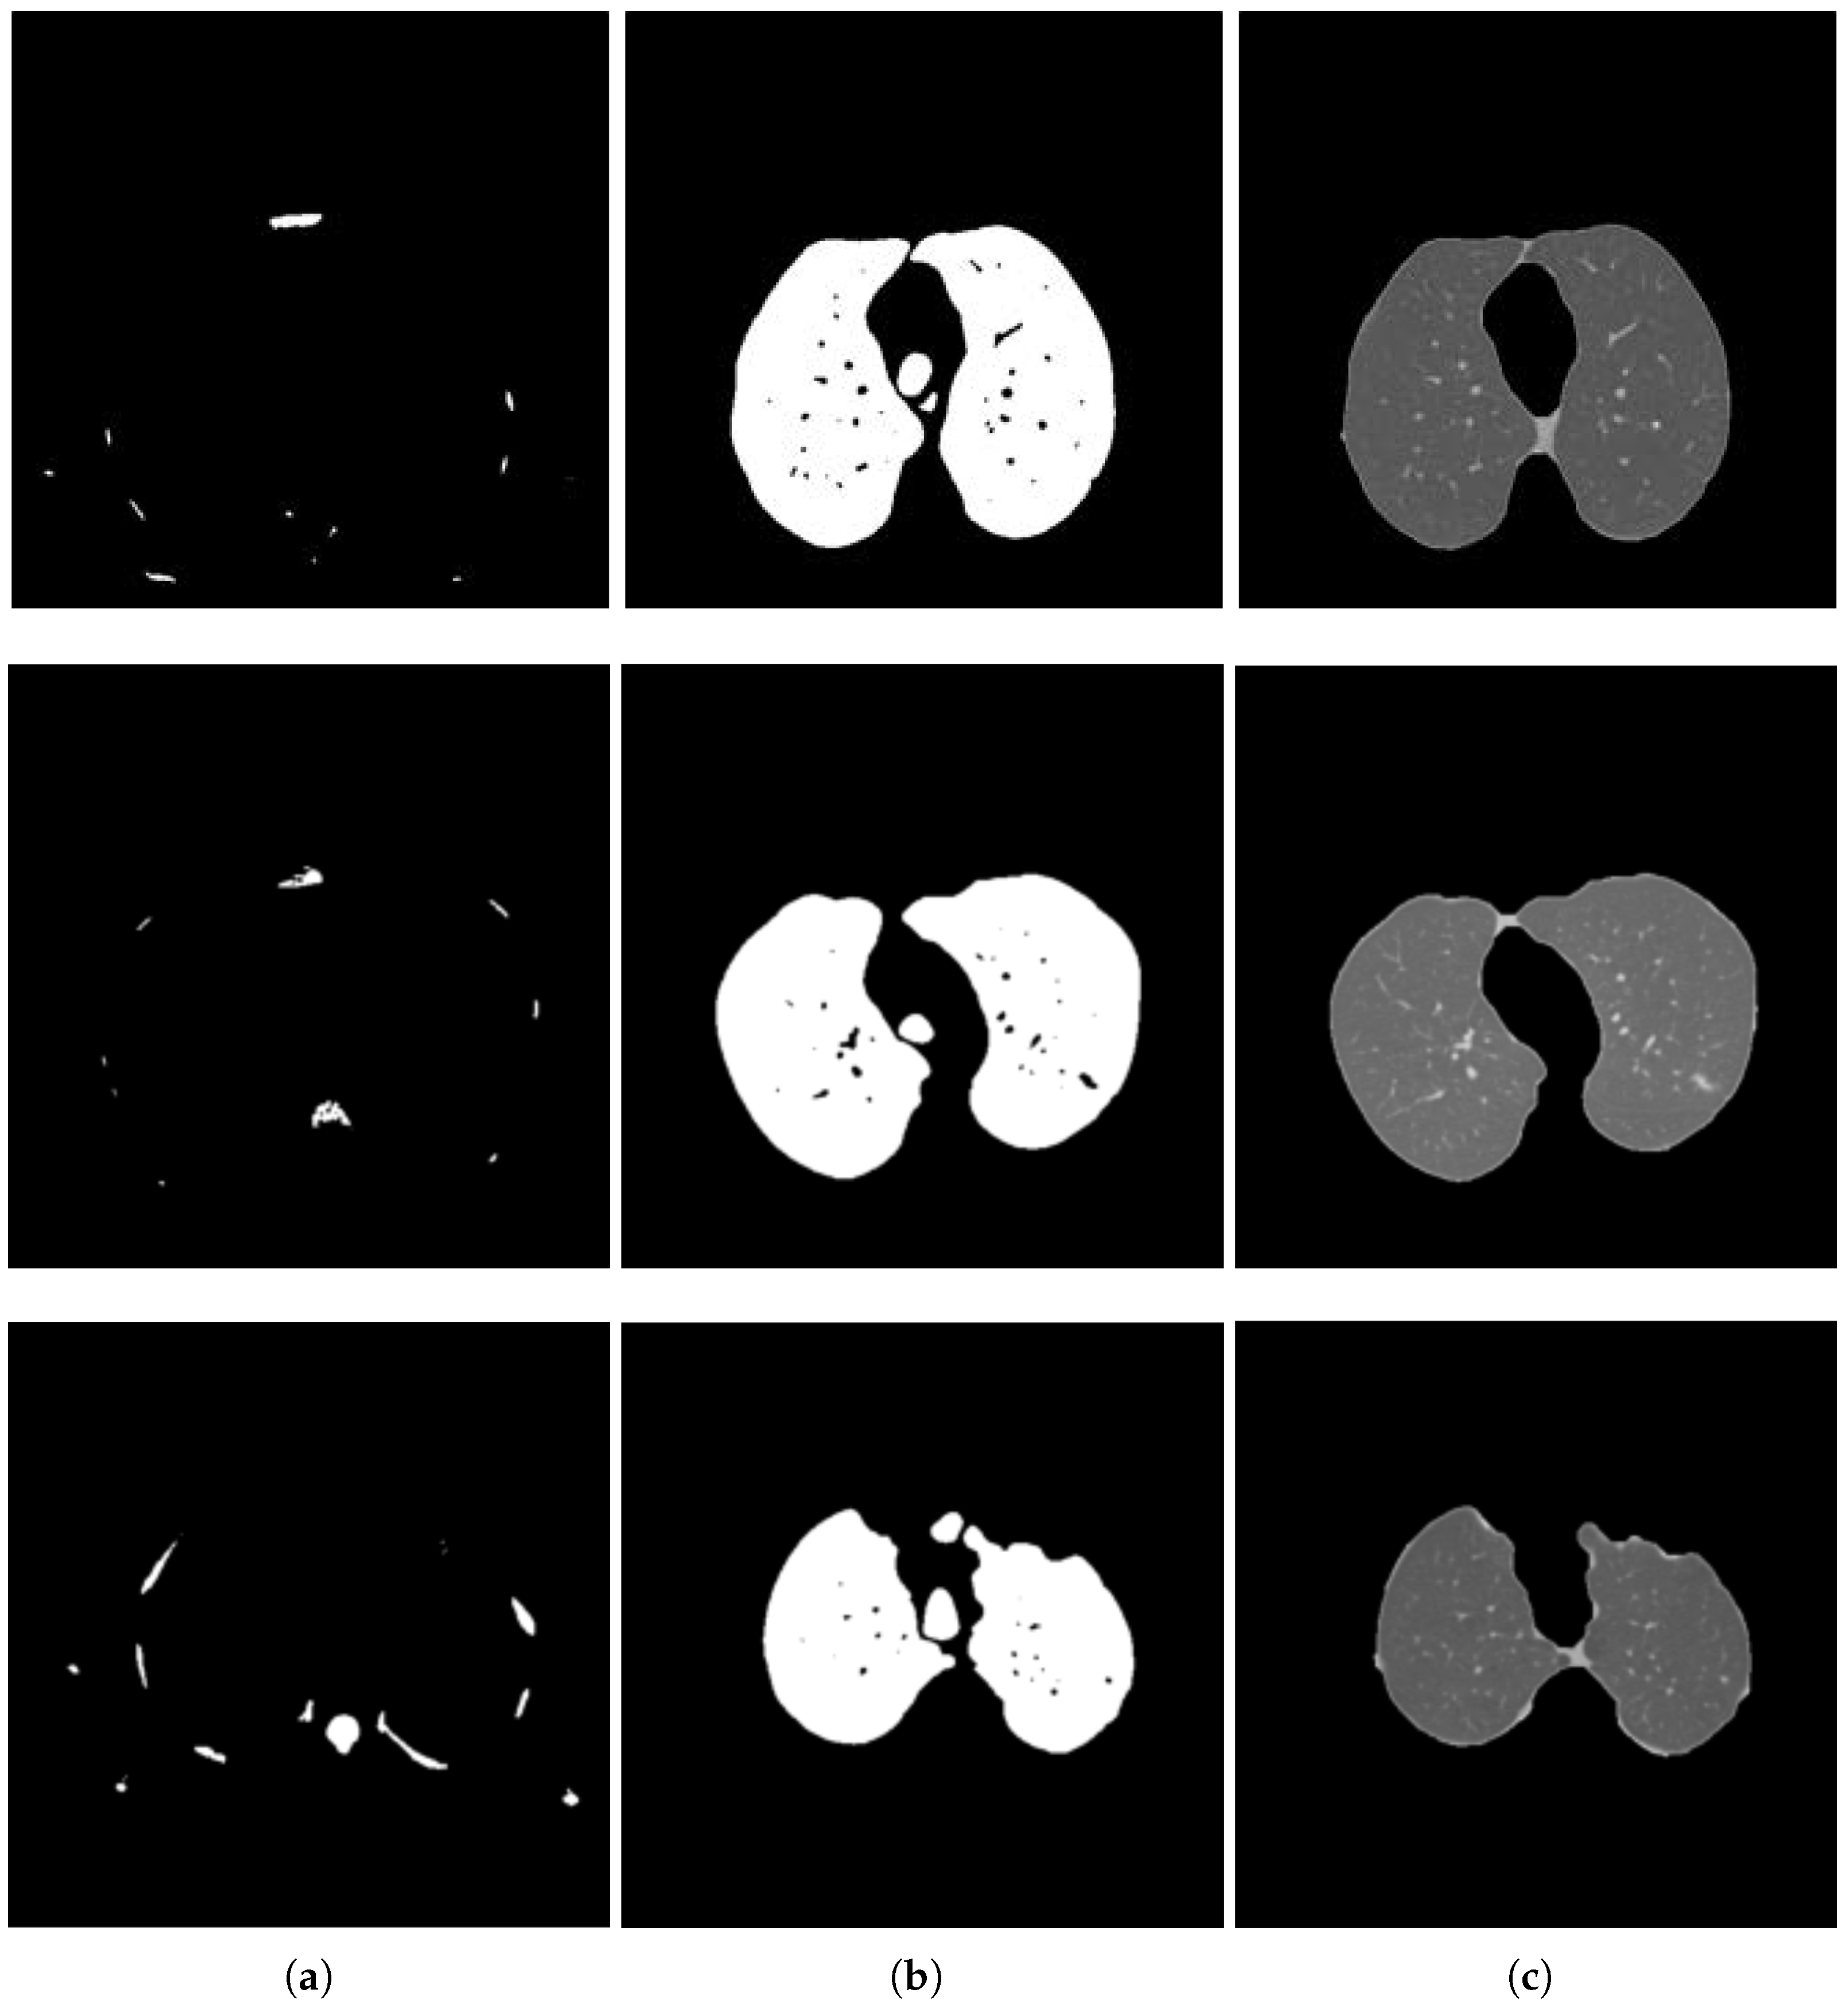

2.2.1. Segmentation in Lung Window

2.2.2. Segmentation in Mediastinal Window